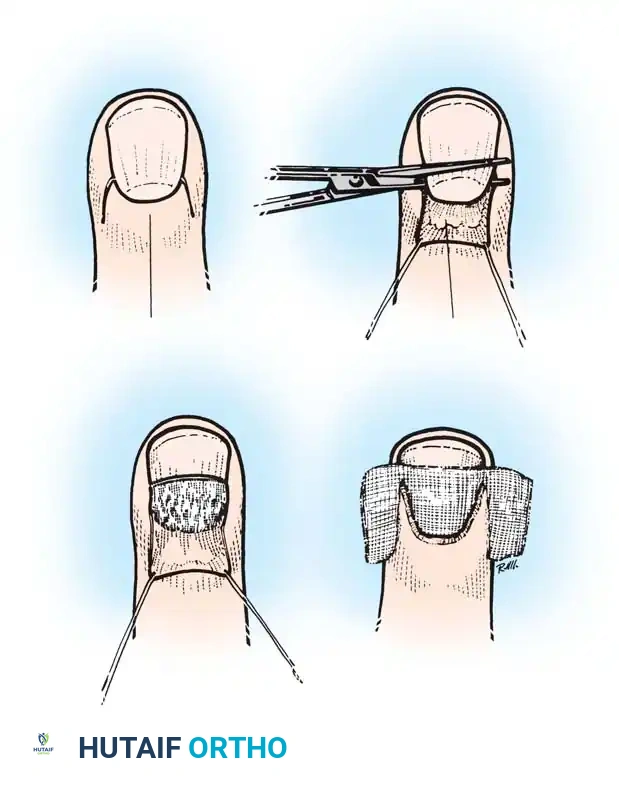

When conservative measures and prolonged medical therapy fail, surgical intervention is indicated. The eponychial marsupialization technique, originally described by Keyser and Eaton and later modified by Bednar and Lane, is the gold standard for recalcitrant chronic paronychia.

The goal of marsupialization is to excise the fibrotic, chronically inflamed tissue of the eponychial fold, thereby decompressing the nail matrix and allowing a new, healthy epithelial barrier to regenerate. Bednar and Lane noted that if concurrent nail irregularities (such as severe transverse ridging or dystrophy) are present, simultaneous removal of the nail plate significantly improves healing rates and prevents recurrence.

🔪 Surgical Technique 75-2: Eponychial Marsupialization

1. Preparation and Anesthesia

* Administer a standard digital block anesthetic using a long-acting agent such as 0.5% bupivacaine to provide extended postoperative pain relief.

* Thoroughly cleanse the entire finger and hand with an appropriate surgical antiseptic (chlorhexidine gluconate or povidone-iodine).

* Drape the hand in a standard sterile fashion. Apply a digital tourniquet to ensure precise visualization of the eponychial microanatomy.

2. The Marsupialization Incision

* Identify the proximal extent of the eponychial fold.

* Using a #15 scalpel blade, excise a crescent-shaped wedge of skin, approximately 3 mm wide, parallel to the curve of the eponychium.

* This crescentic excision must extend fully from the radial border to the ulnar border of the nail fold. The widest portion of the crescent should be at the dorsal midline of the digit.

3. Tissue Resection (Keyser/Eaton vs. Bednar/Lane)

* Keyser and Eaton Approach: Deepen the incision to remove all thickened, fibrotic, and chronically inflamed tissue down to the level of the germinal matrix.

* Bednar and Lane Modification: Carefully excise the skin but leave the underlying subcutaneous fat intact. This modification is believed to protect the delicate germinal matrix from iatrogenic injury while still effectively marsupializing the fold.

4. Nail Plate Management

* Critically evaluate the nail plate. If the nail exhibits significant irregularities, thickening, or detachment, it acts as a nidus for ongoing fungal colonization.

* In such cases, use a Freer elevator or straight hemostat to gently separate the nail plate from the sterile and germinal matrices, and completely avulse the nail.

5. Wound Dressing

* The marsupialized defect is left open to heal by secondary intention; it is never primarily closed.

* Cover the exposed wound bed with a non-adherent, petroleum-bismuth tribromophenate–impregnated gauze (Xeroform).

* If the nail plate was removed, carefully tuck a single layer of this Xeroform gauze beneath the newly marsupialized proximal nail fold to prevent synechiae (adhesions) between the dorsal roof and the germinal matrix.